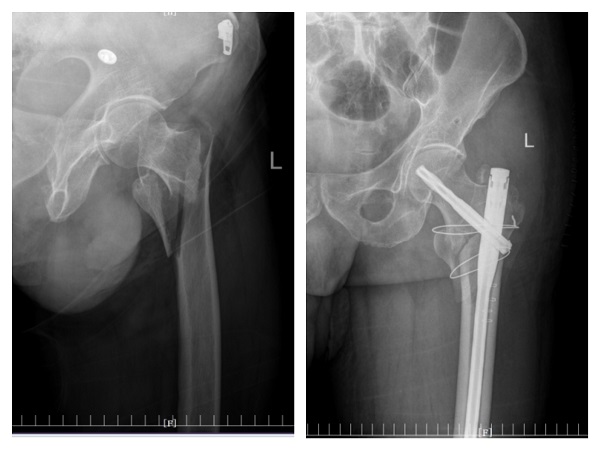

许爷爷今年83岁,不慎摔伤致左髋部疼痛入住二一五医院骨五科,完善检查发现许爷爷新冠病毒检测为阳性,肺部已有感染。由于年事已高,有基础病且合并新冠病毒感染,病情复杂危重,情况非常棘手。骨五科潘建宏主任团队为许爷爷进行了全面细致的病情评估,并请院内相关专家组会诊,制定了有针对性的治疗方案。

入院一周后,肺部感染逐渐得到控制,氧饱和度正常后,潘主任团队为许爷爷进行左侧人工股骨头置换术,手术十分顺利。术后,科室医护人员密切关注老人的神志、呼吸和各项生命体征变化,及时根据病情变化调整治疗方案,并加强肺功能锻炼。术后三天,许爷爷能够在助行器辅助下下床行走,无明显不适,生命体征平稳。在科室医护团队日夜精心的照料下,许爷爷日见好转,说话声音开始响亮,浑身也有了力气,其家属表示深深地感谢,经过半个多月的精心治疗,许爷爷现已康复出院。